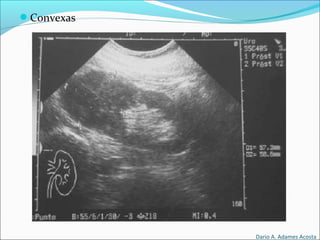

Convexos

Tienen una forma

curva y proporcionan

un formato de imagen

de trapecio.

Se usan en la

exploración

abdominal general y

obstétrica.

Las frecuencias de

trabajo son las

mismas que en las

sondas sectoriales.

Convexas